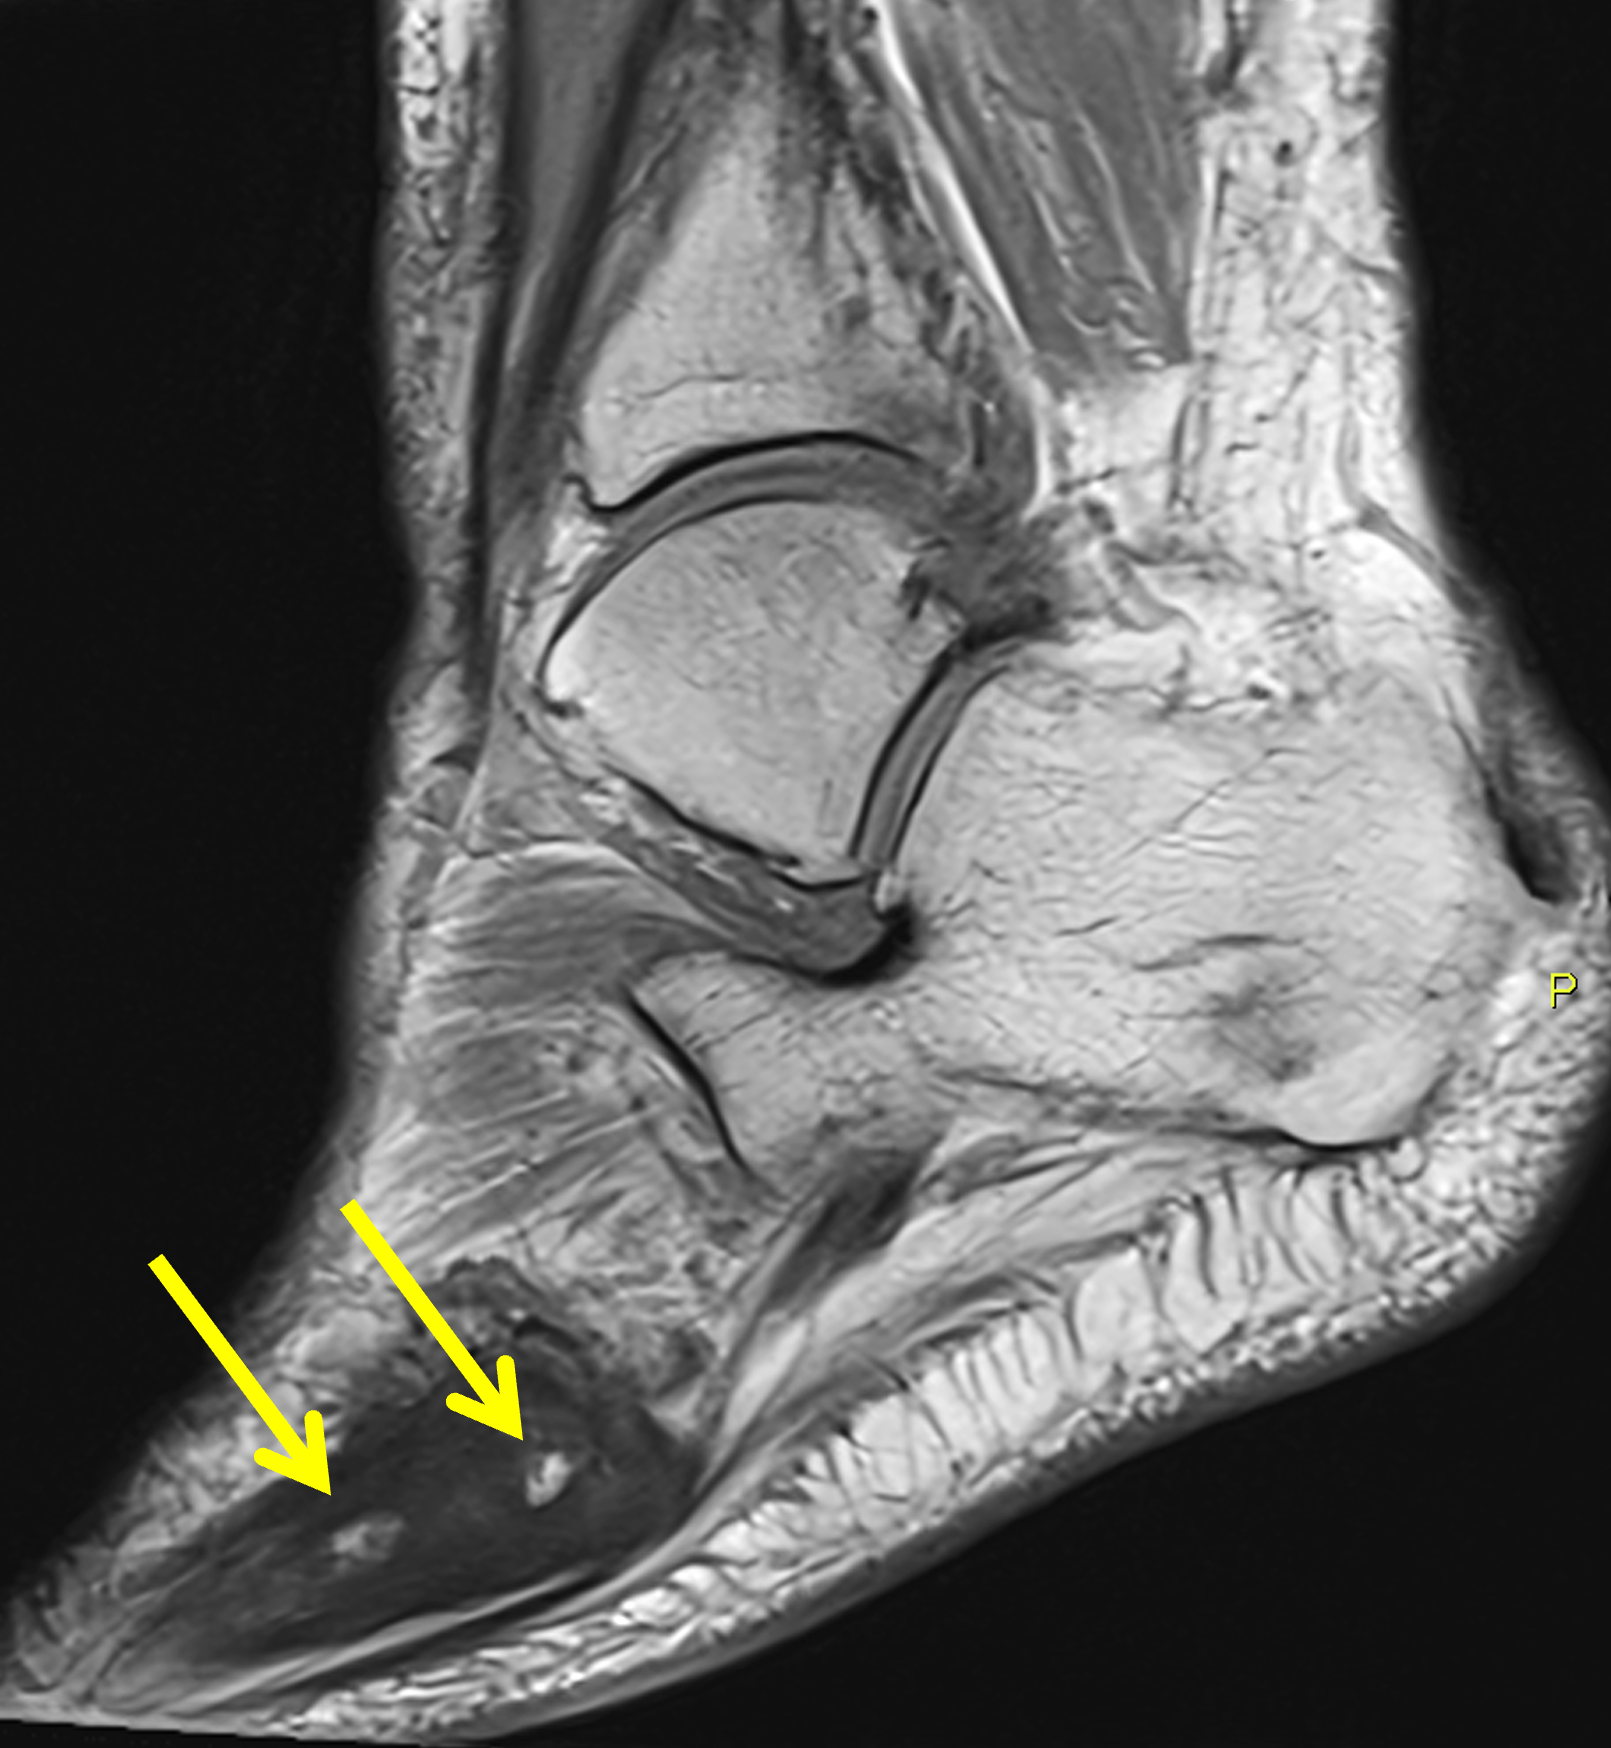

Figure 9: Sclerotic phase Paget disease of the fifth metatarsal, MRI pattern 3. (9A) Sagittal T1-weighted image shows nearly uniform hypointense marrow in the fifth metatarsal, with small islands of preserved marrow fat (arrows), which helps exclude a malignant process. (9B) Sagittal fat-suppressed T2-weighted image shows mildly increased signal intensity throughout the marrow (asterisk). (9C) Dorsoplantar radiograph demonstrates sclerosis throughout the fifth metatarsal, due to cortical and trabecular thickening. Note the bone enlargement and bowing. (9D) Short-axis CT image shows nearly uniform sclerosis throughout the fifth metatarsal.